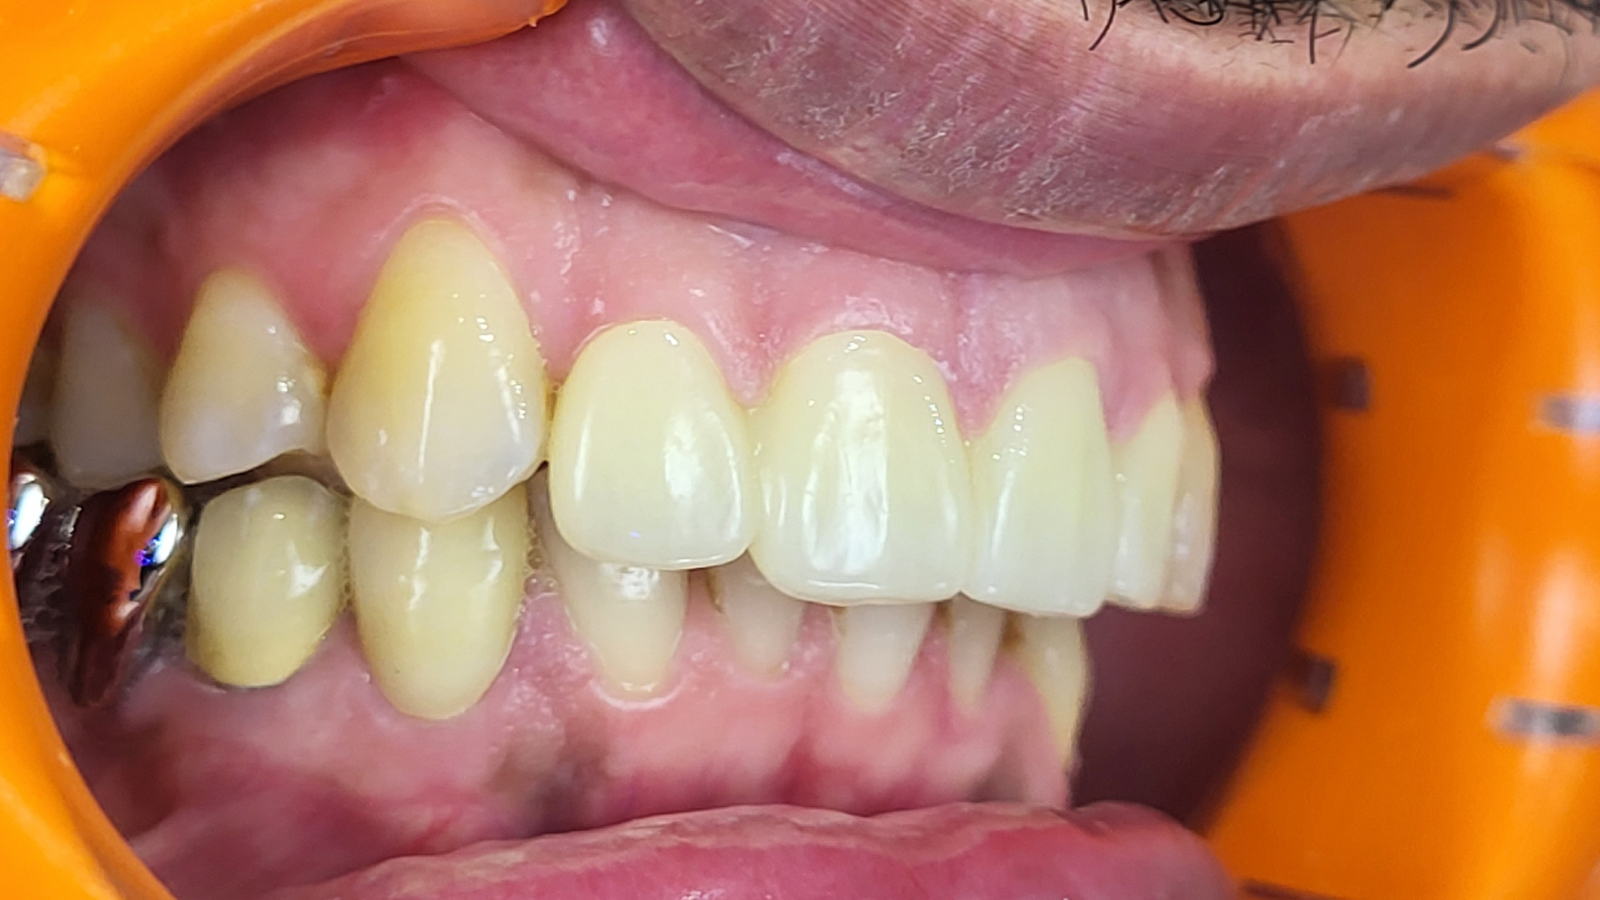

Réhabilitation complète avec mise en charge immédiate (4 implants bas / 6 implants haut)

Le patient se présente avec des dents qui bougent, en haut et en bas.

Nous avons commencé par la mâchoire inférieure avec 4 implants et une mise en charge immédiate.

Trois mois après, le haut a été fait avec le même principe avec 6 implants.

Cette fois-ci, il existait un déficit osseux, résolu par une technique d’expansion sans avoir recours à la greffe d’os.

Les prothèses réalisées sont vissées, ce qui permet de les enlever, les nettoyer une fois par an, ou résoudre n’importe quel problème.